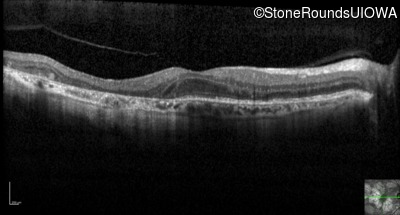

Optical Coherence Tomography - Right - 20/40 -2

Exemplar / OCT Stack

Optical Coherence Tomography - Left - 20/40 +1